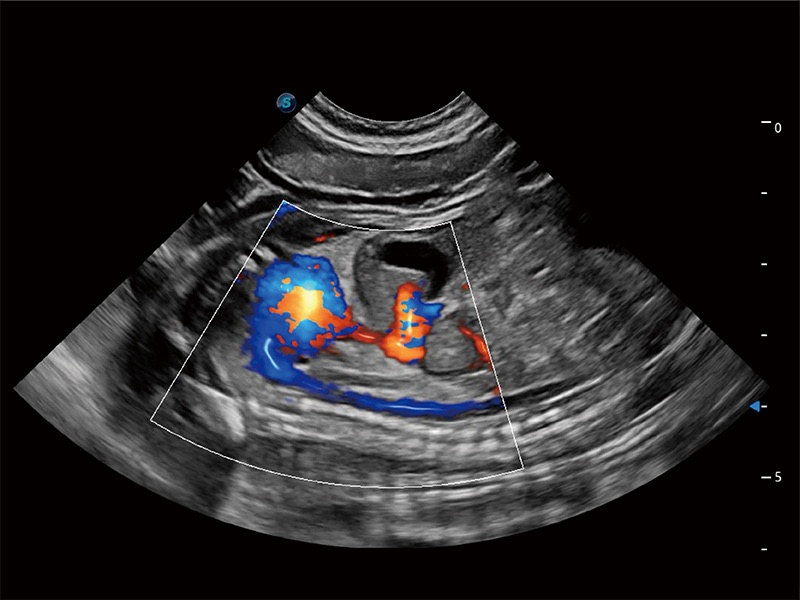

ProPet 80 配備了豐富的心臟探頭群、先進(jìn)的成像技術(shù)和專業(yè)的心臟測量工具,可幫助動物醫(yī)生為不同體型和生理結(jié)構(gòu)的動物提供心臟和心肌功能的全面評估。

實(shí)時用顏色表示心肌組織運(yùn)動,觀察和定量組織的運(yùn)動情況,對快速檢測與評估心肌的灌注和活性、電傳導(dǎo)及心肌收縮和舒張功能等均能提供重要的診斷信息。